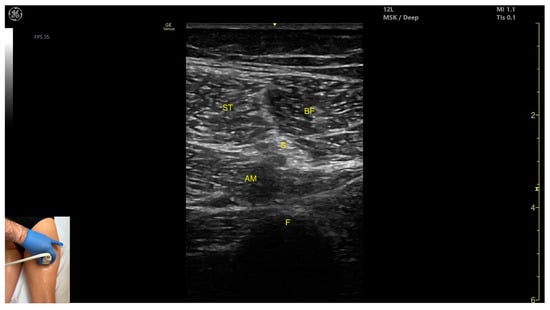

3.10. Semitendinosus (ST)

3.10.1. Overview

3.10.2. Ultrasound Identification

3.10.3. Key Ultrasound Landmarks

- Muscle position: It appears as a superficial muscle mass at this level. It is the second muscle from medial to lateral in the proximal third of the posterior thigh. It is bordered medially by the semimembranosus and laterally by the biceps femoris. The sciatic nerve lies deep and lateral to the ST and deep to the biceps femoris.

- Muscle morphology: The “Mercedes-Benz sign” may be seen—an ultrasound pattern created by the intersection of the fascial planes of the ST, biceps femoris, and adductor magnus, with the sciatic nerve centered between them. A characteristic “Venetian blind” appearance can be observed—this refers to the vertical intramuscular fascia traversing the muscle’s width. It appears as alternating hyperechoic and hypoechoic bands resembling the slats of a Venetian blind, resulting from the regular alignment of muscle fibers and connective septa reflecting ultrasound waves (Video S3).

- External fascia: It features a pronounced fascia that separates it from the subcutaneous layer, adductor magnus, semimembranosus, and biceps femoris, which is crucial for safe BoNT-A injection.

- Dynamic evaluation: During dynamic scanning distally toward the knee joint, the ST decreases in thickness, while the semimembranosus increases. The sciatic nerve maintains its course deep and lateral to the semitendinosus. Muscle contraction is visible during hip extension, knee flexion, and the internal rotation of the leg.

3.11. Biceps Femoris (BF)

3.11.1. Overview

3.11.2. Ultrasound Identification

3.11.3. Key Ultrasound Landmarks

- Muscle morphology: It has two heads: the long head (medial) and the short head (lateral), which can be approached individually, separated by an intramuscular fascia.

- Muscle position: It appears as a superficial muscle mass and is the most lateral muscle in the posterior (flexor) compartment of the thigh at this level. The long head lies adjacent to the sciatic nerve, which runs underneath the muscle.

- External fascia: A pronounced fascia separates the BF from the subcutaneous plane, and from the vastus lateralis and semitendinosus, which is relevant during BoNT-A injections.

- Dynamic evaluation: During dynamic evaluation, scanning proximally toward the hip joint, the long head increases in thickness while the short head decreases. At the mid-thigh, the short head disappears, and the long head reaches its maximum thickness. Scanning distally toward the knee joint, the short head increases in thickness, and the long head decreases. Muscle contraction is visible during hip extension, external rotation, knee flexion, and the external rotation of the leg.